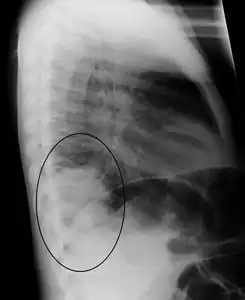

AP CXR showing left lower lobe pneumonia associated with a small left sided pleural effusion

Right lower lobe pneumonia as seen on a lateral CXR